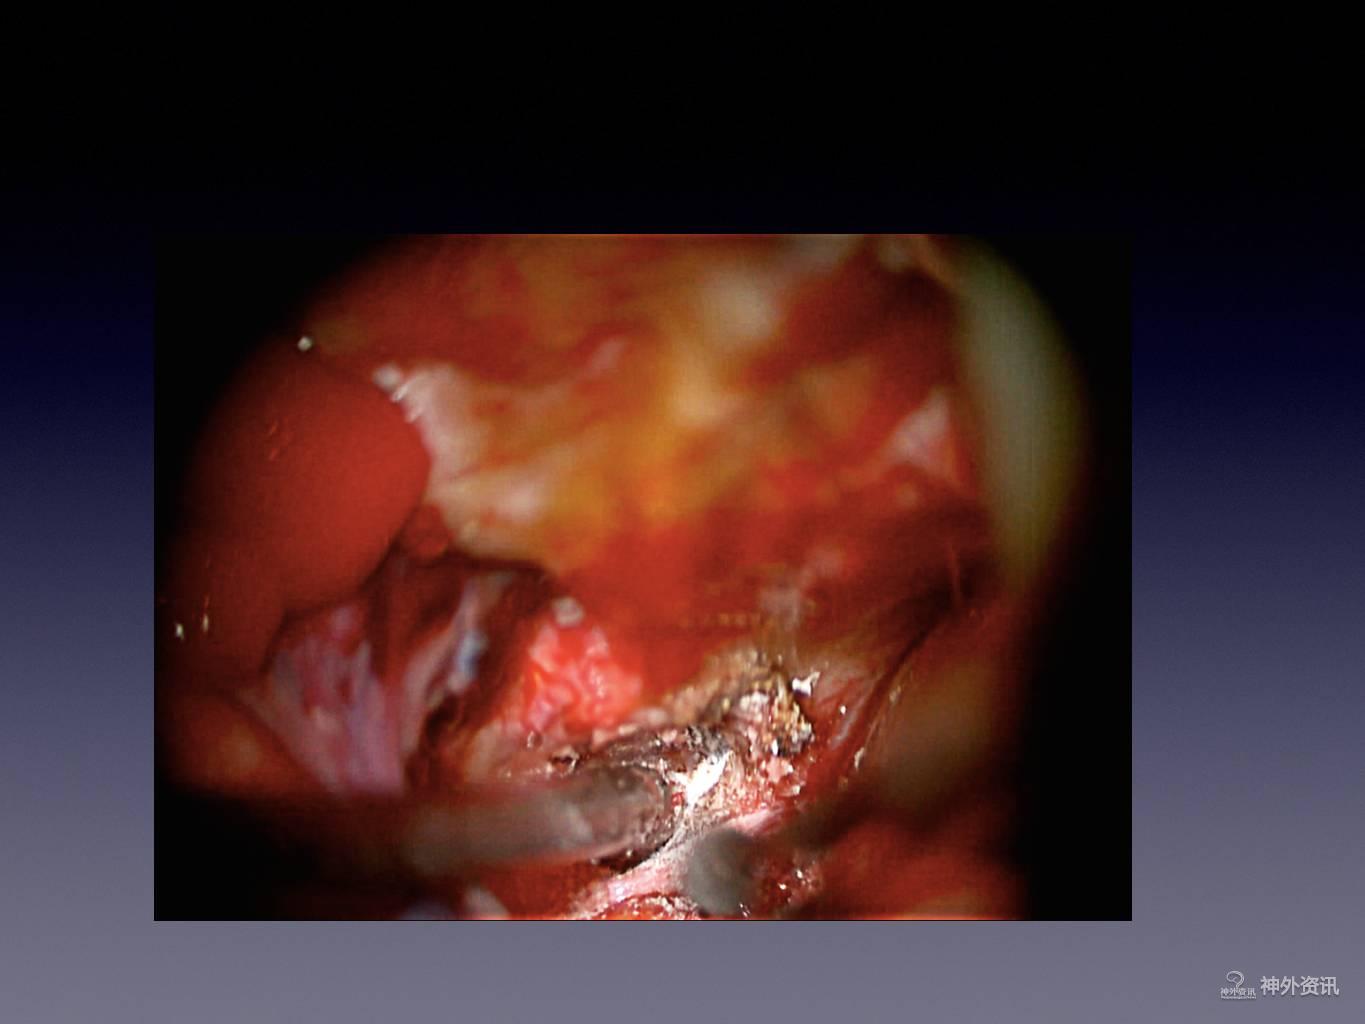

王林教授:床突旁动脉瘤夹闭手术

今天为大家分享的是《正海-妙术视界》第二十二期,由浙江大学医学院附属第二医院神经外科王林教授带来的床突旁动脉瘤夹闭手术,视频非常精彩,欢迎观看。